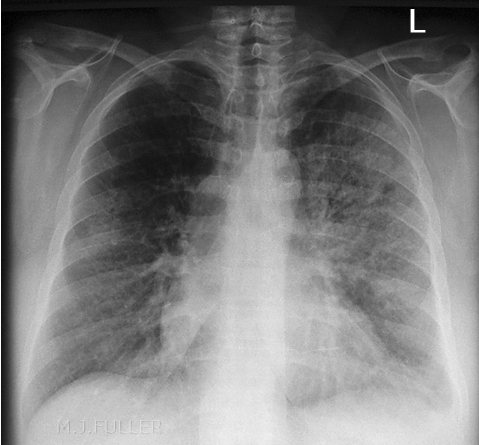

Example 3

Diagnosis

Right lower lobe pneumonia